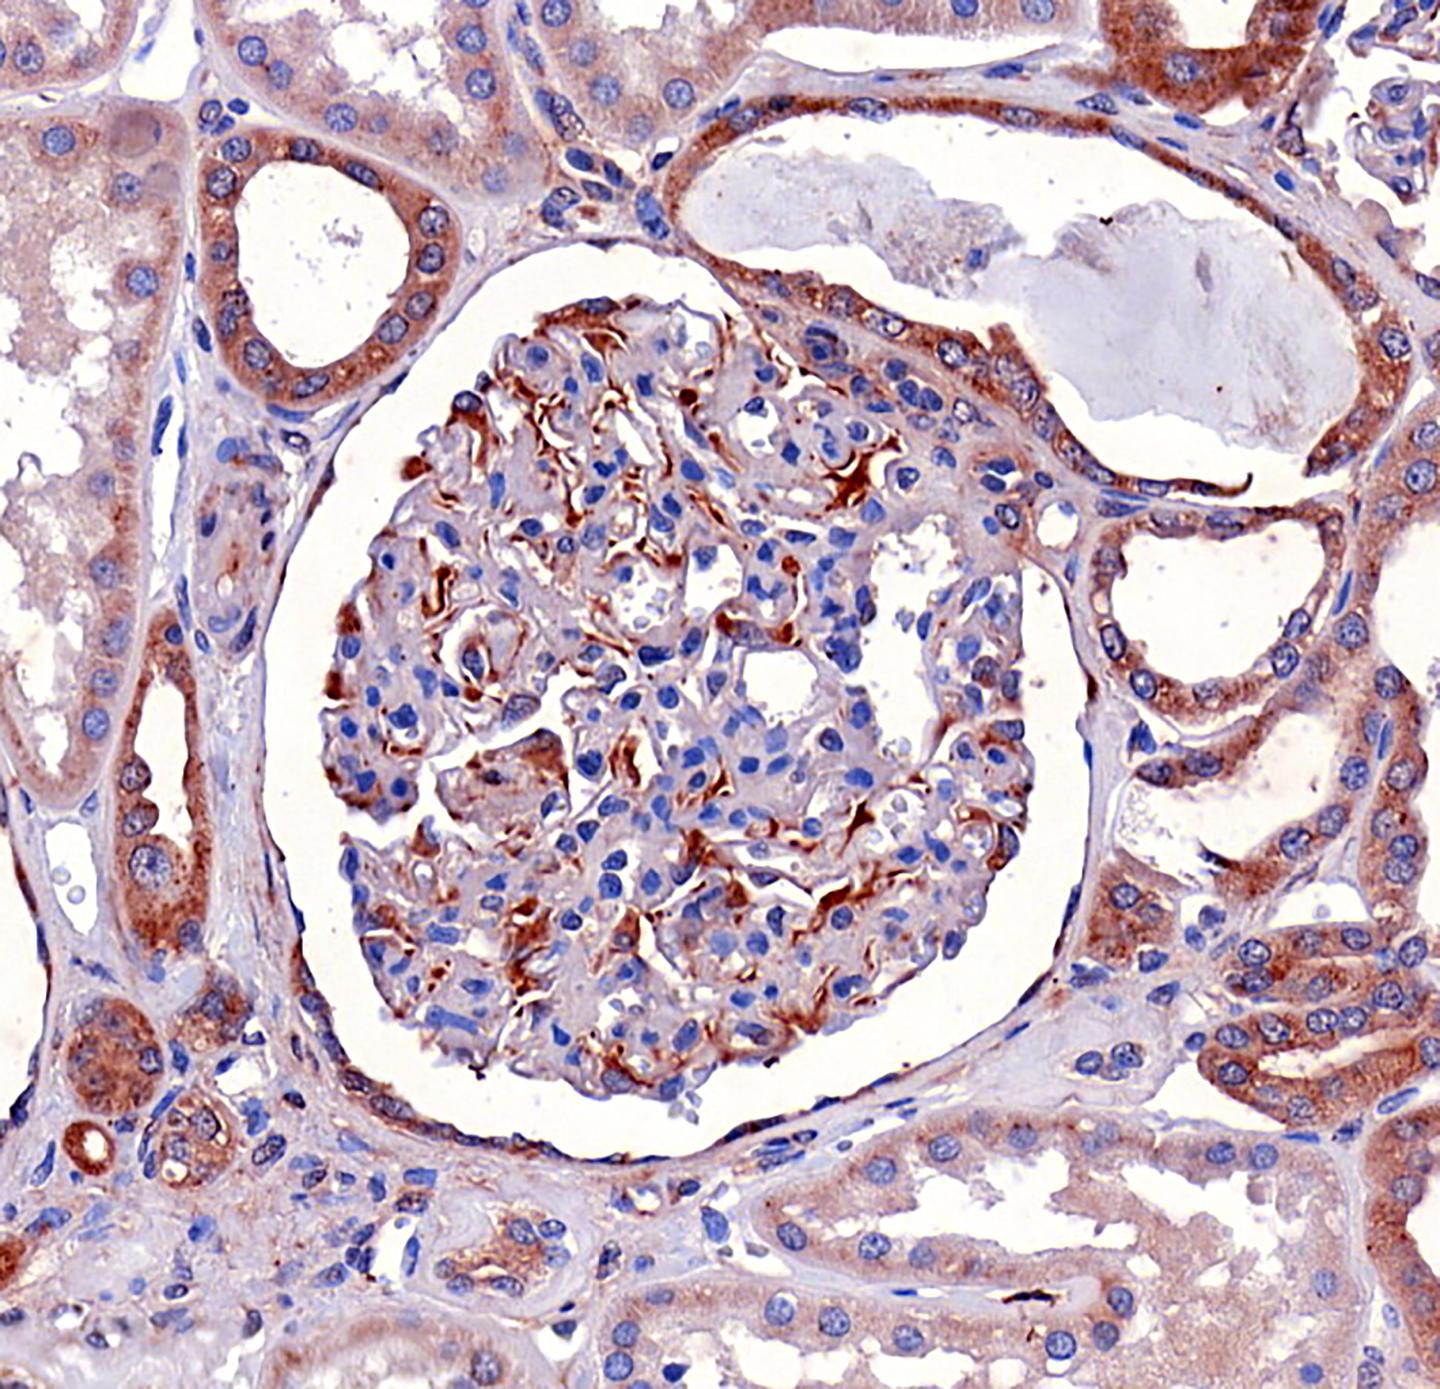

A research group led by Professor Sanna Lehtonen at the University of Helsinki has now demonstrated in cell cultures and in an animal model that metformin directly binds to the lipid phosphatase SHIP2, reducing its activity. The reduction in SHIP2 activity increased glucose uptake in muscle cells and decreased cell death in podocytes, or glomerular epithelial cells.

The lipid phosphatase SHIP2 suppresses the insulin signalling pathway. Prior studies have demonstrated through animal models that individuals suffering from diabetes have elevated levels of SHIP2 in their kidney, muscle and adipose tissue. This reduces the ability of tissue to react to insulin signalling and reduces its glucose uptake. Elevated SHIP2 concentration also increases programmed cell death in podocytes.

In addition to an animal model, Lehtonen's group utilised patient samples in the study. Their analysis revealed that in patients with type 2 diabetes who were not taking metformin, SHIP2 activity in the kidneys was elevated, in addition to which their podocyte loss was remarkable. In patients taking metformin, SHIP2 activity did not deviate from people without diabetes, while podocyte loss was also lower than in patients using another drug therapy.